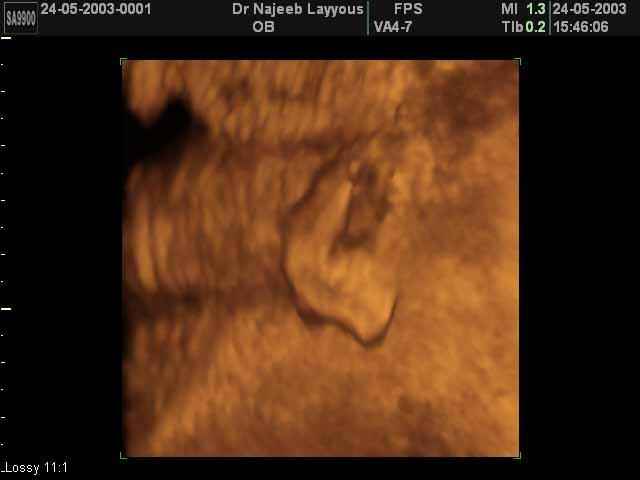

- 3D Photos échographie des parties du fœtus